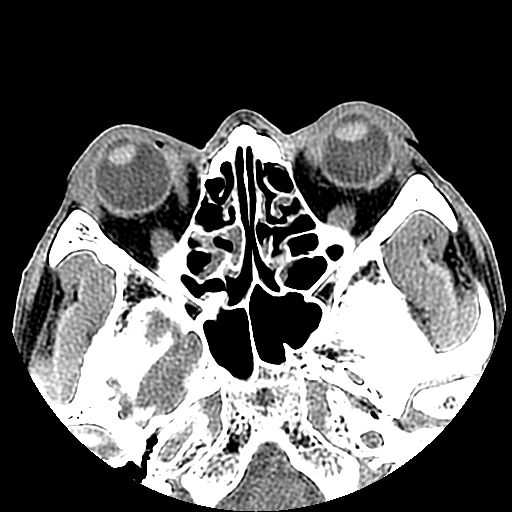

以下是引用liaoqiang在2008-7-16 21:15:00的发言:[br]右侧鼻骨骨折

以下是引用zxd95在2008-7-16 21:39:00的发言:[br]右侧上颌骨额突骨折。[br][br][br][br]